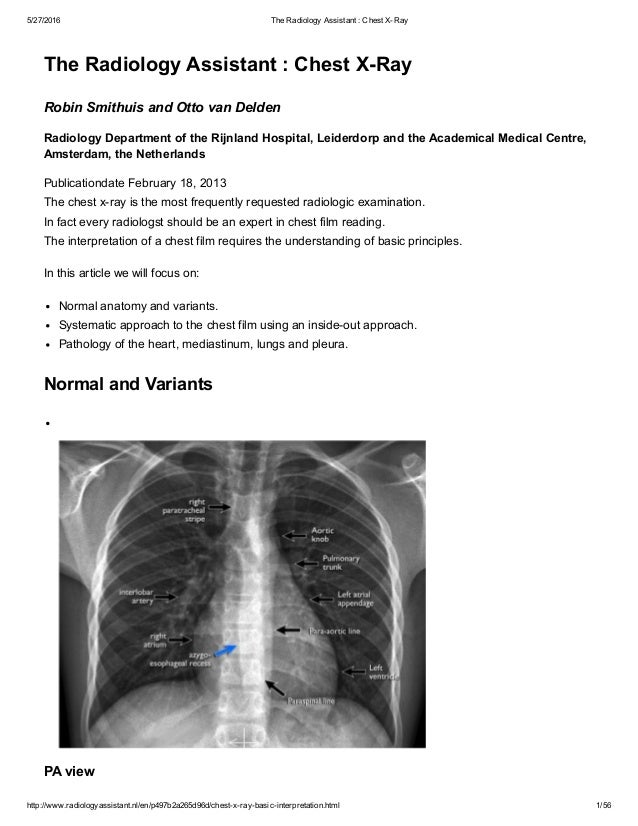

The Radiology Assistant Chest X Ray Basic Interpretation